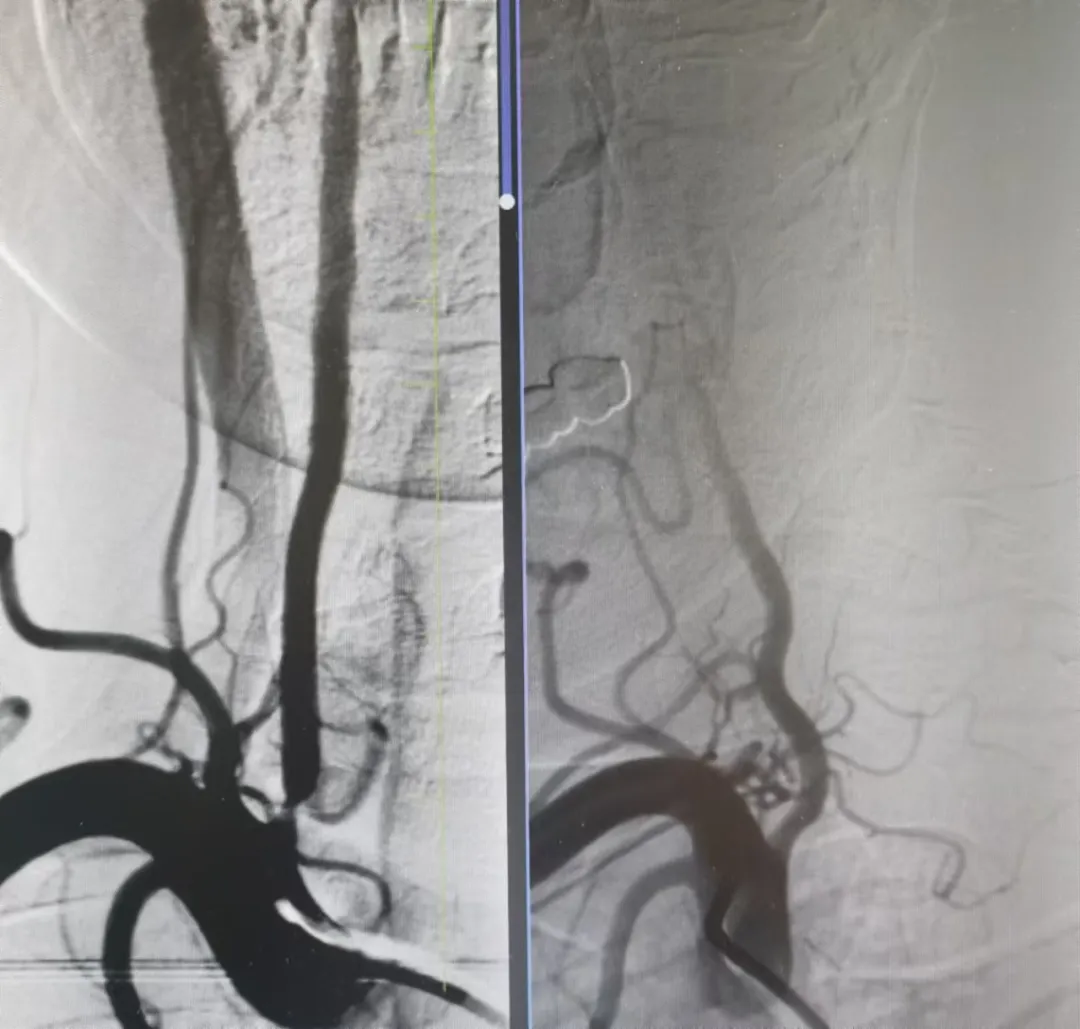

家屬同意后,神經(jīng)介入科團(tuán)隊(duì)迅速給予行腦血管造影,結(jié)果提示:右側(cè)椎動(dòng)脈重度狹窄。朱洪波副主任表示:該處一旦發(fā)生循環(huán)梗死,輕則癱瘓?jiān)诖病⒅貏t昏迷不醒甚至危及生命,建議盡快對(duì)重度狹窄血管積極處理。家屬對(duì)患者病情及治療方案詳細(xì)了解后,決定接受介入手術(shù)治療。

手術(shù)在局麻下施行,通過經(jīng)橈動(dòng)脈入路,予以行右側(cè)椎動(dòng)脈起始處重度狹窄球囊擴(kuò)張術(shù),經(jīng)股動(dòng)脈穿刺,微導(dǎo)絲送入球囊至病變狹窄部位進(jìn)行擴(kuò)張,擴(kuò)張后造影提示狹窄部位擴(kuò)張滿意,基底動(dòng)脈血流明顯改善,手術(shù)順利結(jié)束。術(shù)后陳大叔上述癥狀完全恢復(fù),大叔妻子感激地說:“感謝國文醫(yī)院的積極救治,來的時(shí)候老陳都暈的無法走路,現(xiàn)在都能自己行走了,太感謝了。”